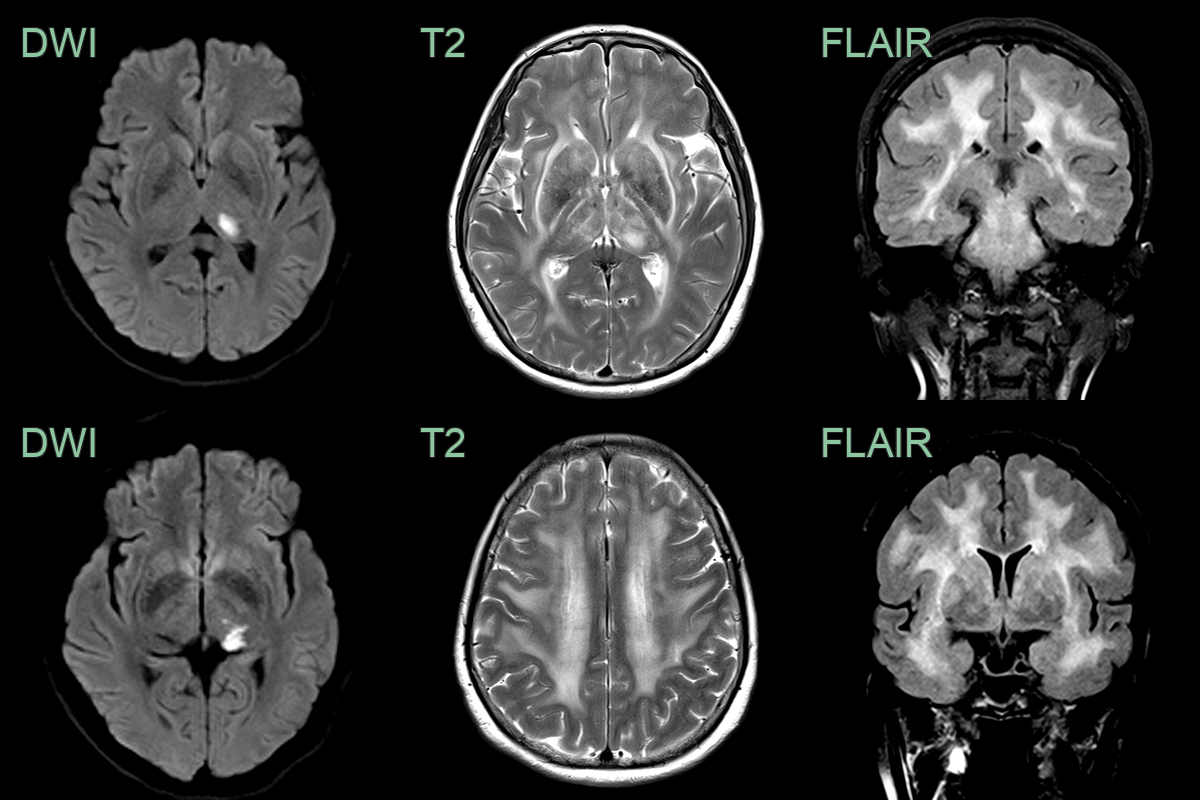

• 50-year-old patient presented with a homonymous hemianopia and mixed sensory and motor deficits.

• MRI showed an acute left thalamic infarct and a diffuse leukoencephalopathy that involved the external capsules and anterior temporal lobes.